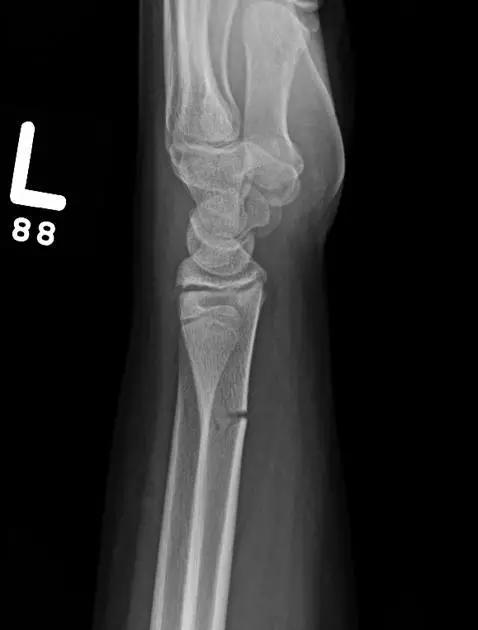

10. Galeazzi 骨折(盖氏骨折)

桡骨干下 1/3 骨折合并尺骨小头脱位。

盖氏骨折正侧位(来源:Orthobullets)